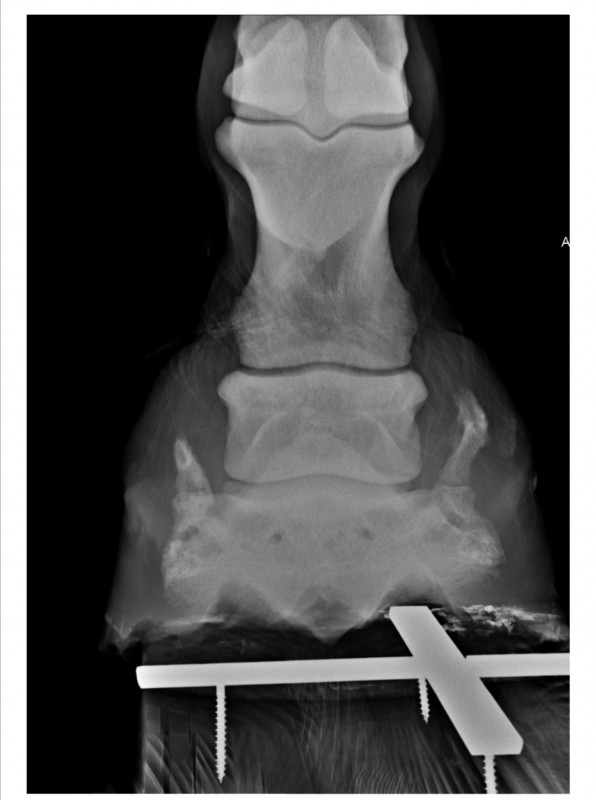

Résultat : arthrose en face antérieure de la 2ème phalange et ossification des cartilages ungulaires. D'après la véto, inutile de faire des radios de l'autre pied. Pour elle c'est sur qu'il y a la même chose, peut-être en moins développé mais présent quand même. C'est parait-il la "maladie des chevaux de trait"

marechal05 Oui j'ai fait des radios de l'antérieur droit en 2017 suite à une boiterie. La véto n'avait pas pensé nécessaire d'en faire de l'antérieur gauche qui d'après elle devait très certainement avoir les mêmes problèmes : arthrose sur la face antérieure de la 2ème phalange et ossification des cartilages ungulaires.

En Septembre 2019 j'en ai fait faire quand même de l'antérieur gauche et effectivement les mêmes constatations ! Par contre j'en ai pas refait de l'antérieur droit à ce moment là et c'est celui qui pose problème aujourd'hui donc... Ça vaut peut-être le coup d'en refaire pour voir si ça a évolué.

Antérieur droit Mars 2017

Antérieur gauche Septembre 2019